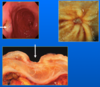

L: top = Barrett’s glandular epithelium; bottom = normal stratified squamous epithelium

R: top = normal stratified squamous epithelium; bottom = Barrett’s glandular epithelium. Intestinal metaplasia within oesophageal glandular mucosa